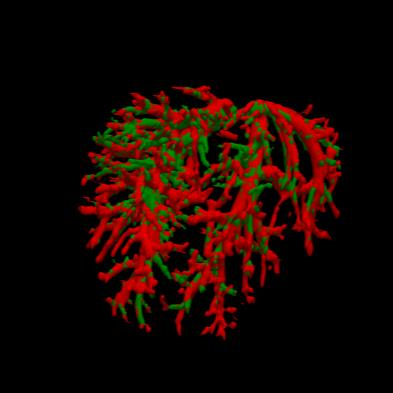

Manually segmenting the hepatic vessels from Computer Tomography (CT) is far more expertise-demanding and laborious than other structures due to the low-contrast and complex morphology of vessels, resulting in the extreme lack of high-quality labeled data. Without sufficient high-quality annotations, the usual data-driven learning-based approaches struggle with deficient training. On the other hand, directly introducing additional data with low-quality annotations may confuse the network, leading to undesirable performance degradation. To address this issue, we propose a novel mean-teacher-assisted confident learning framework to robustly exploit the noisy labeled data for the challenging hepatic vessel segmentation task. Specifically, with the adapted confident learning assisted by a third party, i.e., the weight-averaged teacher model, the noisy labels in the additional low-quality dataset can be transformed from "encumbrance" to "treasure" via progressive pixel-wise soft-correction, thus providing productive guidance. Extensive experiments using two public datasets demonstrate the superiority of the proposed framework as well as the effectiveness of each component.